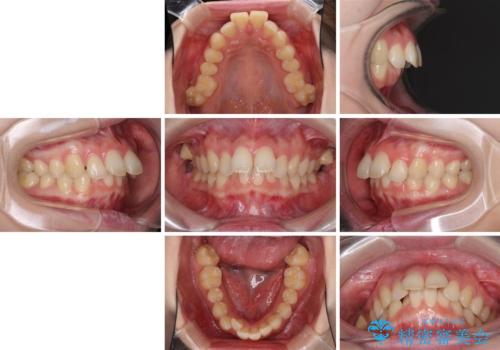

- 口元の突出感を気にして来院された患者様です。

左右ともに上顎奥歯が外を向き、下顎奥歯が内側に倒れているシザーズバイトであったため、補助装置により改善することとしました。

上下の咬み合わせは、下顎に対して上顎が相対的に前方にあったため、奥歯のシザーズバイト改善後に上顎左右第一小臼歯2本を抜歯し、上顎前突を改善していくこととしました。